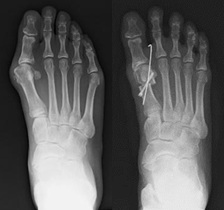

外反母趾:足の親指が外側に曲がる変形 強剛母指:親指の付け根の関節が変形し、硬くなって痛む疾患 変形性足関節渉:外傷後や加齢により足関節の軟骨がすり減り、痛みや可動域の制限が生じる疾患 関節リウマチによる足部変形 など当科の特長と主な取り組み

当外来では、患者さん一人ひとりのライフスタイルや活動性を考慮し、保存療法(靴・インソール指導)から、手術(外反母趾手術や人工関節置換術など)まで、最適な治療法を提供します。